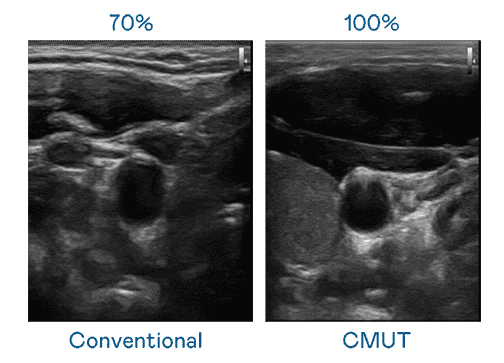

CMUT 技术是一种用电容式微机电元件来产生超音波讯号的技术。。。。与传统 PZT 压电式技术相比,,,,CMUT 频宽增加 30%,,,,更宽频的超音波讯号让影像解析度大幅提升,,,,是实现高影像品质医疗超音波扫描、、、促进精准医疗发展的关键技术。。。。

大频宽带来超清晰影像

超音波影像的解析度高低,,首先取决于探头能发出的讯号频宽。。。。2121非凡 CMUT 可提供高清晰的超音波讯号,,,,提供高频宽、、高灵敏度、、、影像纹理细节更高的超音波影像,,,,协助医护人员缩短影像判读时间及利用精准的医疗影像进行诊断。。。。